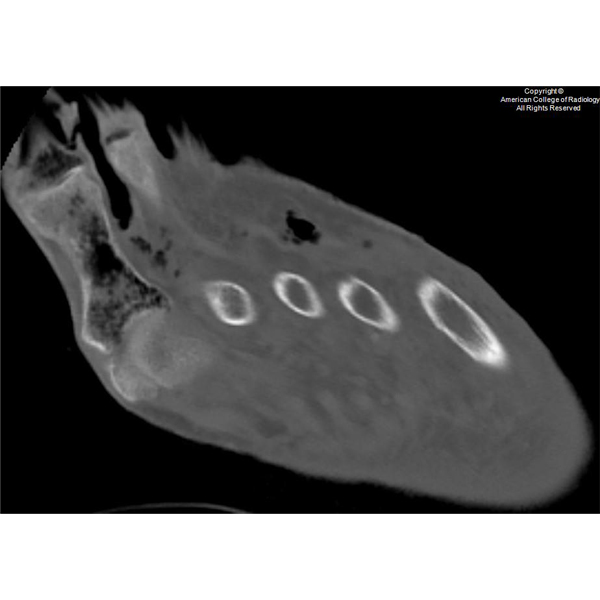

22yo F presents w/ chief complaint of anterior knee pain Swipe to view complete case Courtesy @piper_long, David Young, DO & @nick_strle | Oklahoma State Univ #radiology #AOCR #MedEd #RadRes #RadFellow #radiologist #radiologylearning #radiologylife #caseoftheweek

22yo F presents w/ chief complaint of anterior knee pain

Swipe to view complete case

Courtesy @piper_long, David Young, DO & @nick_strle | Oklahoma State Univ